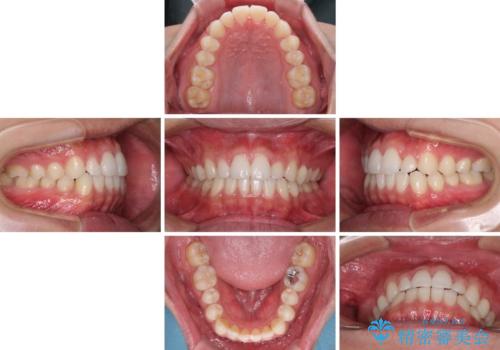

- 前歯のデコボコとクロスバイトを治したいとのことで来院された患者様です。

上下顎ともに歯列全体の側方拡大を行い、下顎前歯はIPR(歯と歯の間を削る)によってデコボコとクロスバイトが解消するように設計し、インビザラインにより治療を行うこととしました。

2年弱で終了する予定でしたが、途中来院されなかった時期があり、その後舌側転位している前歯を動かせるところまで動かしたいとのことで4年ほど治療を継続されました。